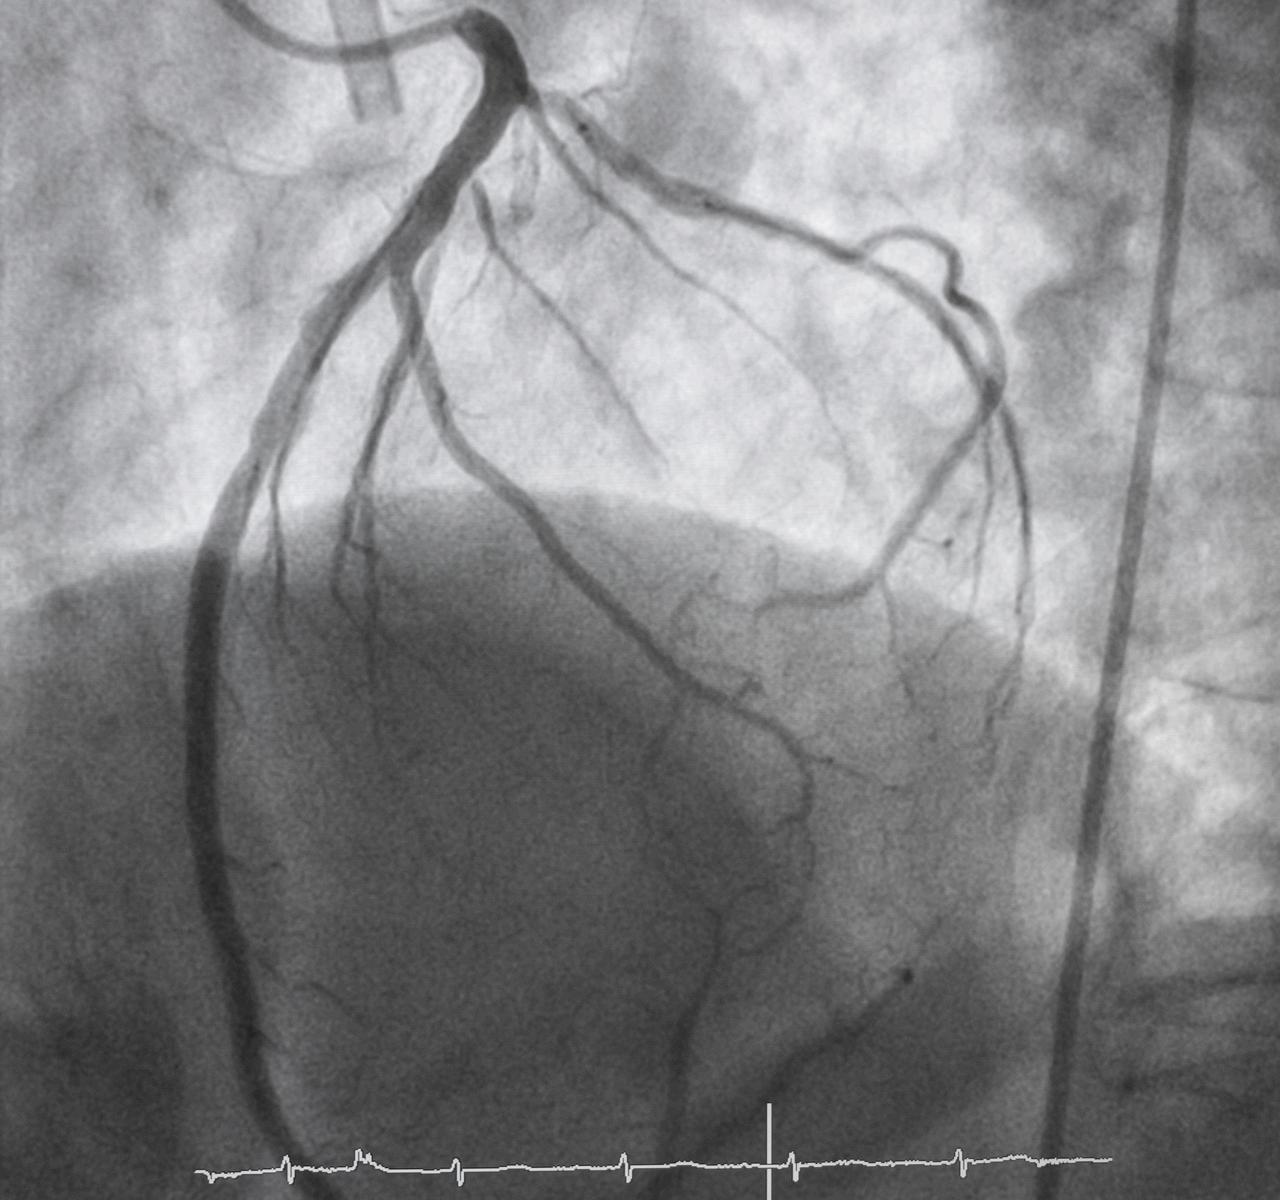

Eitt dæmi er svokallað MINOCA (Myocardial Infarction with Non-Obstructive Coronary Arteries) eða hjartaáfall án þess að greinileg stífla sjáist í stórum kransæðum við kransæðamyndatöku Þetta er algengara hjá konum en körlum Ástæðan getur verið örrof í litlum veggskellum, æðakrampi, bólga í hjartavöðva, truflun í smáæðum eða aðrar fínlegar breytingar sem ekki sjást sem klassísk stífla

Annað fyrirbæri sem sést hjá konum er svokallað SCAD (spontaneous coronary artery dissection) eða sjálfsprottið rof í vegg kransæða. Í SCAD myndast rof eða aðskilnaður í æðaveggnum, blóð safnast inn í vegginn og býr til þrengsli í æðinni sem getur stöðvað blóðflæði til hluta hjartans Meðal sjúklinga með SCAD eru konur í miklum meirihluta, og sjúkdómurinn greinist hjá ungum eða miðaldra konum sem ekki falla í hefðbundinn “há-áhættuhóp”. Þess vegna getur verið hætta á að einkenni séu afskrifuð sem kvíði, vöðvaverkir eða þreyta vegna álags.

Smáæðasjúkdómur (coronary microvascular dysfunction, CMVD) er einnig oftar greindur hjá konum Þá virðast stóru kransæðarnar vera opnar, en blóðflæði í örsmáum æðum í hjartavöðvanum sjálfum er truflað

Konan finnur fyrir brjóstverk og mæði, en kransæðamyndataka sýnir ekki endilega þrengingar í stórum æðum Það getur leitt til þess að vandinn er ekki skoðaður nánar þar sem einkennin eru væg eða almenn, þótt raunverulegur súrefnisskortur í hjartavöðva sé til staðar